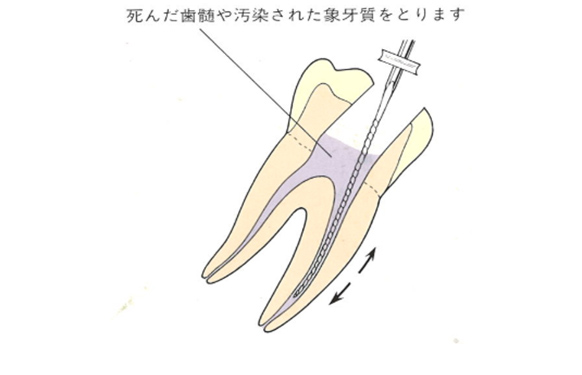

虫歯菌に侵された神経(歯髄)や汚染された象牙質をリーマー、Kファイル、Hファイルなどを使用して取り除いていきます。

ファイルやリーマーを使用して神経を取ります。

神経を取ったらそれで治療が終了ではありません。